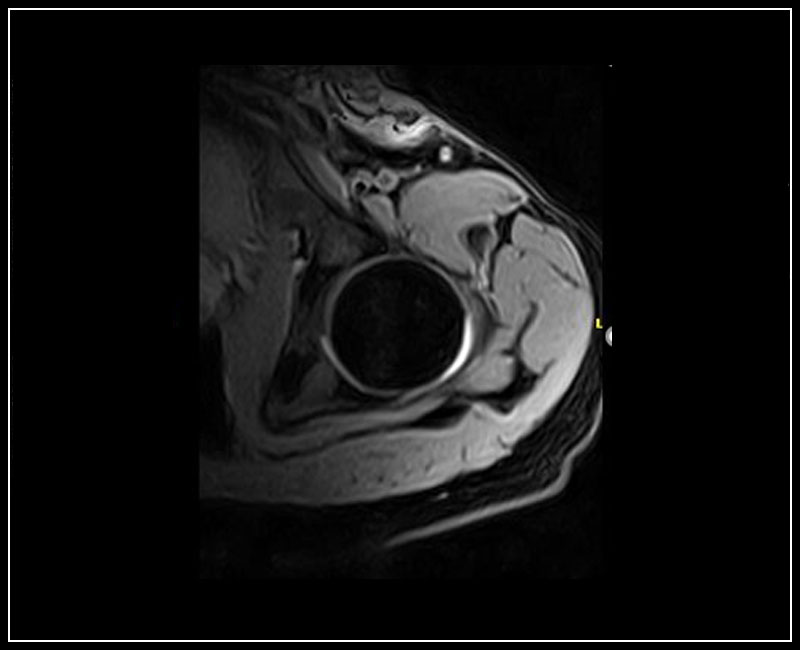

G-scan Brio obsahuje kompletní sadu  cívek speciálně navržených pro zobrazování MSK, což zaručuje velmi vysokou citlivost a pohodlí pacienta.

• Velký výběr specializovaných cívek MSK, celkem 10 různých cívek zaměřených na všechny anatomické oblasti

Klinické snímky